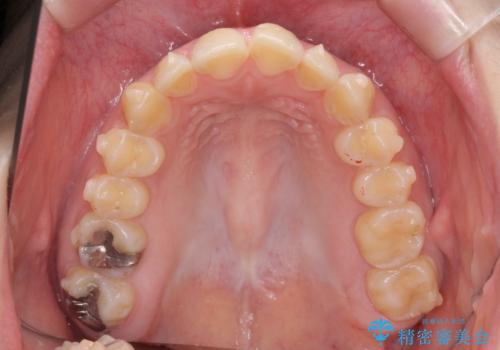

マウスピース矯正で行う出っ歯の治療

- 飛び出したように見える前歯の改善を求めて来院されました。

元々、セラミッククラウンですぐに歯並びを改善したいと希望されていましたが、目立たないマウスピース矯正治療のご提案を行なったところ矯正治療による歯並びの改善を選択されました。

矯正治療を行ったことで出っ歯の改善とともに安定した噛み合わせも手に入れることができました。